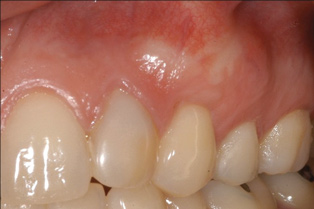

Fig 2. Miller Class I recession on tooth No. 11 (Fig 1) treated with tuberosity CTG (Fig 2). Note this CTG (which is the tuberosity CTG from Fig 5) was placed before the practitioner developed thinning techniques, so a keloid-like appearance was observed even 1 year after grafting.

Figure 2

A complication in using CT from the tuberosity reported in the literature is a tendency for clinicians to harvest tissue that is too thick.12 This can result in a keloid-like appearance similar to what may occur with an EPG. This excess thickness can be unesthetic (Figure 1 and Figure 2) and subsequently require a gingivoplasty to remove the superfluous tissue.12 This problem may perhaps be alleviated with proper thinning of the graft prior to insertion into the recipient area.

Dense CT presumably is less susceptible to shrinkage than less-dense CT. One problem with denser CT may be the need for a longer amount of time to blend in with adjacent non-grafted areas. Due to density, a CT graft might never completely blend in and always demonstrate an unesthetic keloid-like appearance. Therefore, with tuberosity tissue, adjusting the tissue thickness prior to placement of the graft is highly clinically relevant. This may be why periodontists have been reluctant to use tuberosity tissue as CT. Palatal tissue has less-dense CT than tuberosity tissue and, therefore, the authors hypothesize and have observed, shrinks more. Because palatal tissue has been the predominant tissue used in CTG, clinicians have become used to the shrinkage associated with the palatal CT and may not realize the need to thin a dense CTG to prevent a keloid-like appearance. Thus, in the past when a tuberosity was used for this purpose, if it was not properly trimmed it would have frequently resulted in an unesthetic keloid-like appearance. The tuberosity CTG should be trimmed to 1 mm to 1.5 mm thick to avoid the need for a future procedure to adjust tissue thickness for esthetics (Figure 3 and Figure 4, Figure 16 and Figure 17).